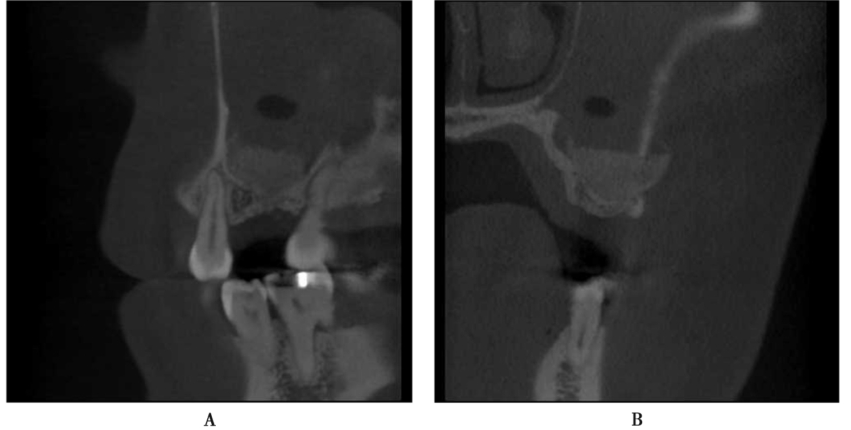

因为B6根尖和牙周炎症较重,拔牙后没有即刻行拔牙位点保护术。拔牙2个月后,外提升术前CBCT示骨质缺损明显,剩余骨量不足以进行种植体植入(图18)。

图18 同一患者拔牙后2个月CBCT,骨量明显不足A.矢状位;B冠状位;C水平位

在B6、B7外提升术的同时,进行了牙槽嵴顶的GBR。术后CBCT示窦底和牙槽嵴顶均填入人工骨粉,骨量增加明显。由于不能获得良好的初期稳定性,没有同期植入种植体(图19)。

图19 完成骨增量后CBCT示骨增量明显A.矢状位;B.冠状位;C.水平位